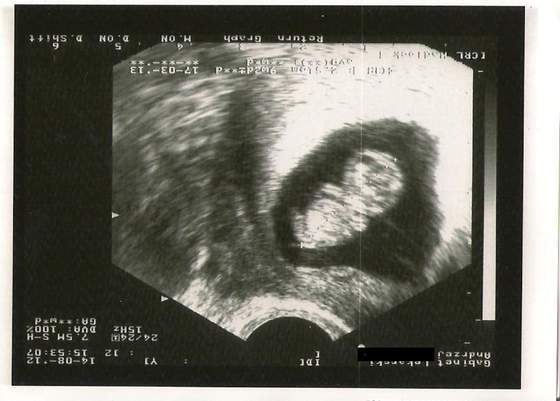

To chyba dla mnie najfajniejszy na razie temat forum. Wasze zdjęcia aż mi buźkę rozweselają jak widzę te kruszynki. Też jestem marcówka. USG genetyczne mam dopiero wyznaczyć (od 1 do 19 września powinnam zrobić). Ale 6-go sierpnia będac na wizycie, która miała potwierdzić gdzie ciąża sie zagnieździła (bo było zagrożenie ponownej pozamacicznej) okazało się , że wszystko jest ok, serduszko biło jak oszalałe. Poniżej fotka. Zielone krzyżyki pokazują długość. Wtedy byłam w 7 tygodniu i 4 dniu ciąży.